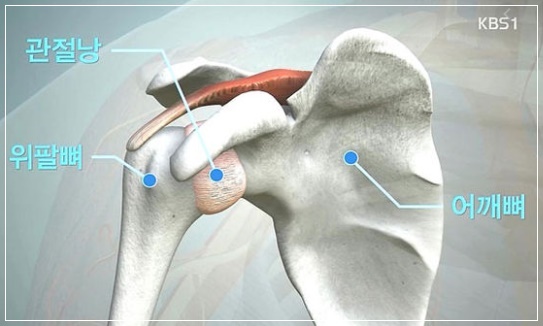

오십견은 어깨가 결리거나 통증을 느끼는 병으로 통증이 있는 쪽으로 누우면 어깨 통증이 더욱 악화되기도 하고 갑작스레 팔을 올리는 동작만으로도 자지러질 정도의 통증이 생기는 경우도 있습니다. 여기서 질환이 한 단계 더 발전하면 통증과 함께 어깨를 쉽게 움직이기 어렵고 어깨가 굳어지며, 이 단계는 보통 4~12개월 정도 지속됩니다. 주로 팔을 들거나 손을 뒤로 할 때 통증이 있고 특히 야간에 통증이 심해지는 경우가 많습니다.

오십견은 덜 사용하는 어깨(오른손잡이의 경우 왼쪽 어깨)에 잘 생깁니다. 따라서 평상시에 스트레칭을 자주 해주는 것이 질환 예방에 도움이 됩니다. 특히 갑상샘 질환자나 당뇨 환자의 경우 발병률이 높기 때문에 평소 갑상선 호르몬 수치나 혈당을 잘 관리해야 합니다. ‘회전근개 손상’은 어깨를 과하게 사용하거나 잘못된 자세에서 잘 나타납니다. 접영, 테니스, 배드민턴 등 팔을 어깨 위로 올리는 동작이 많은 운동 후에는 어깨 통증이 심해지지 않는지 확인하는 것이 좋습니다.